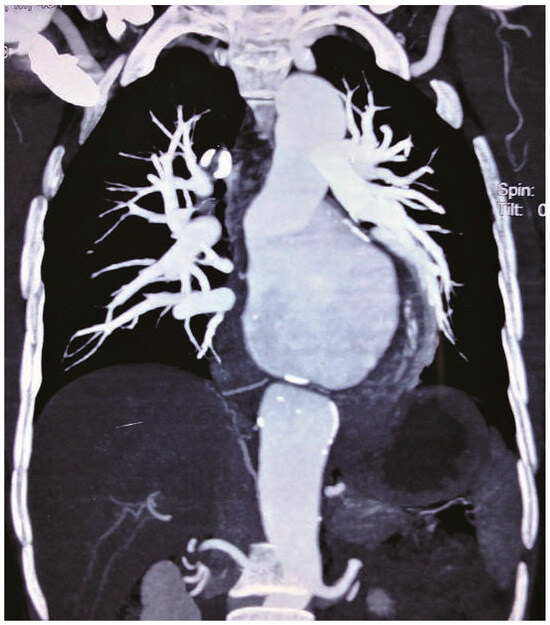

Case report. A 63-year-old hypertensive male presented with atypical chest discomfort and breathlessness on exertion [...]